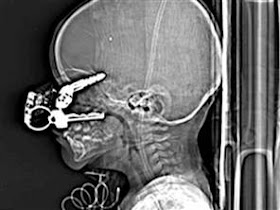

I heard a passing reference on the news this morning about a boy who survived keys lodged in his eye socket (x-ray below). It reminded me of the classic story of Phineas Gage. Yesterday, I had an x-ray taken of my tooth, which I had the office e-mail to me so I could upload it. I've been unsuccessful with that so far, but offer the following strange images and stories: